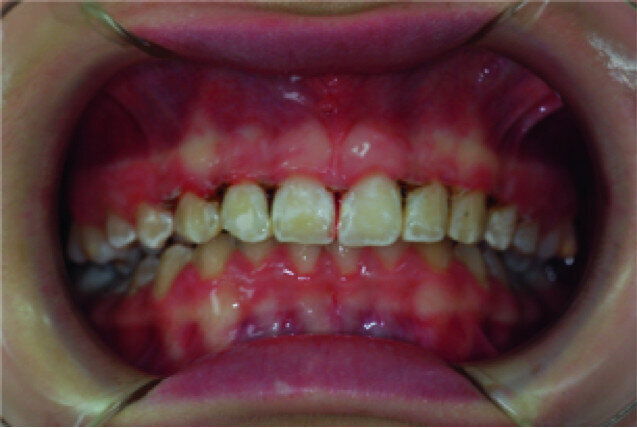

Clinical view, showing gingival enlargement, just before the debonding procedure.

A 14-year-old female patient was referred to our department by the orthodontics unit because, at the end of fixed orthodontic treatment, she had developed gingival enlargement in the upper arch (Fig. 1), probably related to the fast closure of the spaces associated with very poor oral hygiene due to bleeding during toothbrushing. Just after the removal of the appliance, a topical anaesthetic (EMLA, AstraZeneca) was applied to the gingivae (Fig. 2) and a gingivectomy was performed using a diode laser (XD-2, Fotona) according to the technique of removal of the inter dental papillae (Fig. 3). The parameters used were as follows: a wavelength of 808 nm, 3 W in continuous wave, a 320 μm fibre in contact mode. The intervention had a duration of 375 seconds, and the patient did not feel any pain (Fig. 4). After the intervention, the patient did not take any kind of pain medication, and the healing process was completed in five days (Fig. 5).